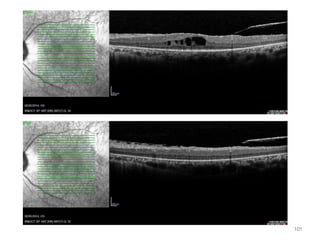

101

102

1

103

2. 1 yr later after rx

104